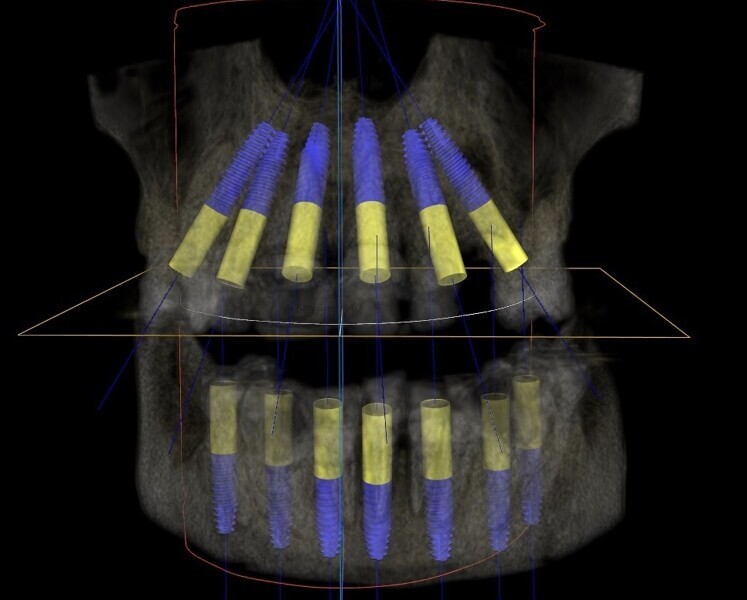

Fig. 9: 3DDX virtual treatment plan for the maxilla and mandible.